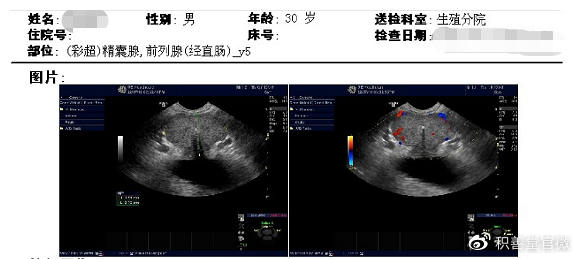

附件:

前列腺大小为41*27*31mm,内见多个强回声斑;

超声提示:前列腺钙化灶